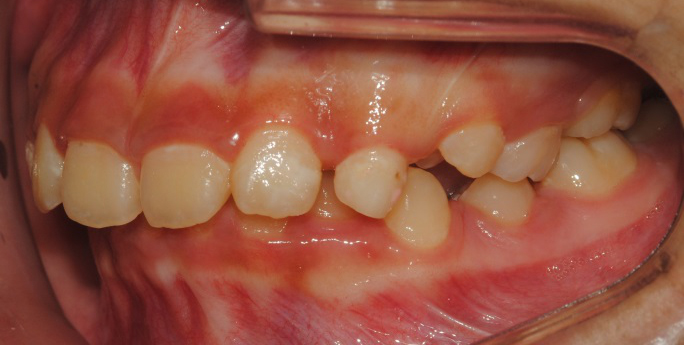

°ú°³±³ÇÕ°ú ¹«ÅÎ,ÅΰüÀýÀ» ÁÖ¼Ò·Î ³»¿øÇÏ¿© ÅμºÀå ¾ÇÁ¤ÇüÀåÄ¡¸¦ ÀÌ¿ëÇÏ¿© Ä¡·áÁßÀΠȯÀÚ·Î Ä¡·á½ÃÀÛ½ÃÁ¡ ±âÁØÀ¸·Î ÇöÀç ۰¡ ¾à 8cmÁ¤µµ ¼ºÀåÇÏ¿´½À´Ï´Ù. (Âü°í·Î 2³âÂ÷ ¿©µ¿»ý°ú ۰¡ 7-9cmŰ Â÷À̳²)